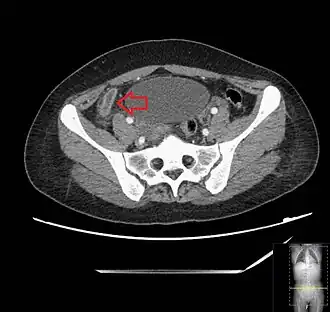

CT scan showing acute appendicitis

A CT scan demonstrating acute appendicitis (note the appendix has a diameter of 17.1 mm and there is surrounding fat stranding).

A fecalith marked by the arrow that has resulted in acute appendicitis.

Where it is readily available, computed tomography (CT) has become frequently used, especially in people whose diagnosis is not obvious on history and physical examination. Although some concerns about interpretation are identified, a 2019 Cochrane review found that the sensitivity and specificity of CT for the diagnosis of acute appendicitis in adults was high.[63] Concerns about radiation tend to limit use of CT in pregnant women and in children, especially with the increasingly widespread usage of MRI.[64][65]

The accurate diagnosis of appendicitis is multi-tiered, with the size of the appendix having the strongest positive predictive value, while indirect features can either increase or decrease sensitivity and specificity. A size of over 6 mm is both 95% sensitive and specific for appendicitis.[66]

However, because the appendix can be filled with fecal material, causing intraluminal distention, this criterion has shown limited utility in more recent meta-analyses.[67] This is as opposed to ultrasound, in which the wall of the appendix can be more easily distinguished from intraluminal feces. In such scenarios, ancillary features such as increased wall enhancement as compared to adjacent bowel and inflammation of the surrounding fat, or fat stranding, can be supportive of the diagnosis. However, their absence does not preclude it. In severe cases with perforation, an adjacent phlegmon or abscess can be seen. Dense fluid layering in the pelvis can also result, related to either pus or enteric spillage. When patients are thin or younger, the relative absence of fat can make the appendix and surrounding fat stranding difficult to see.[67]